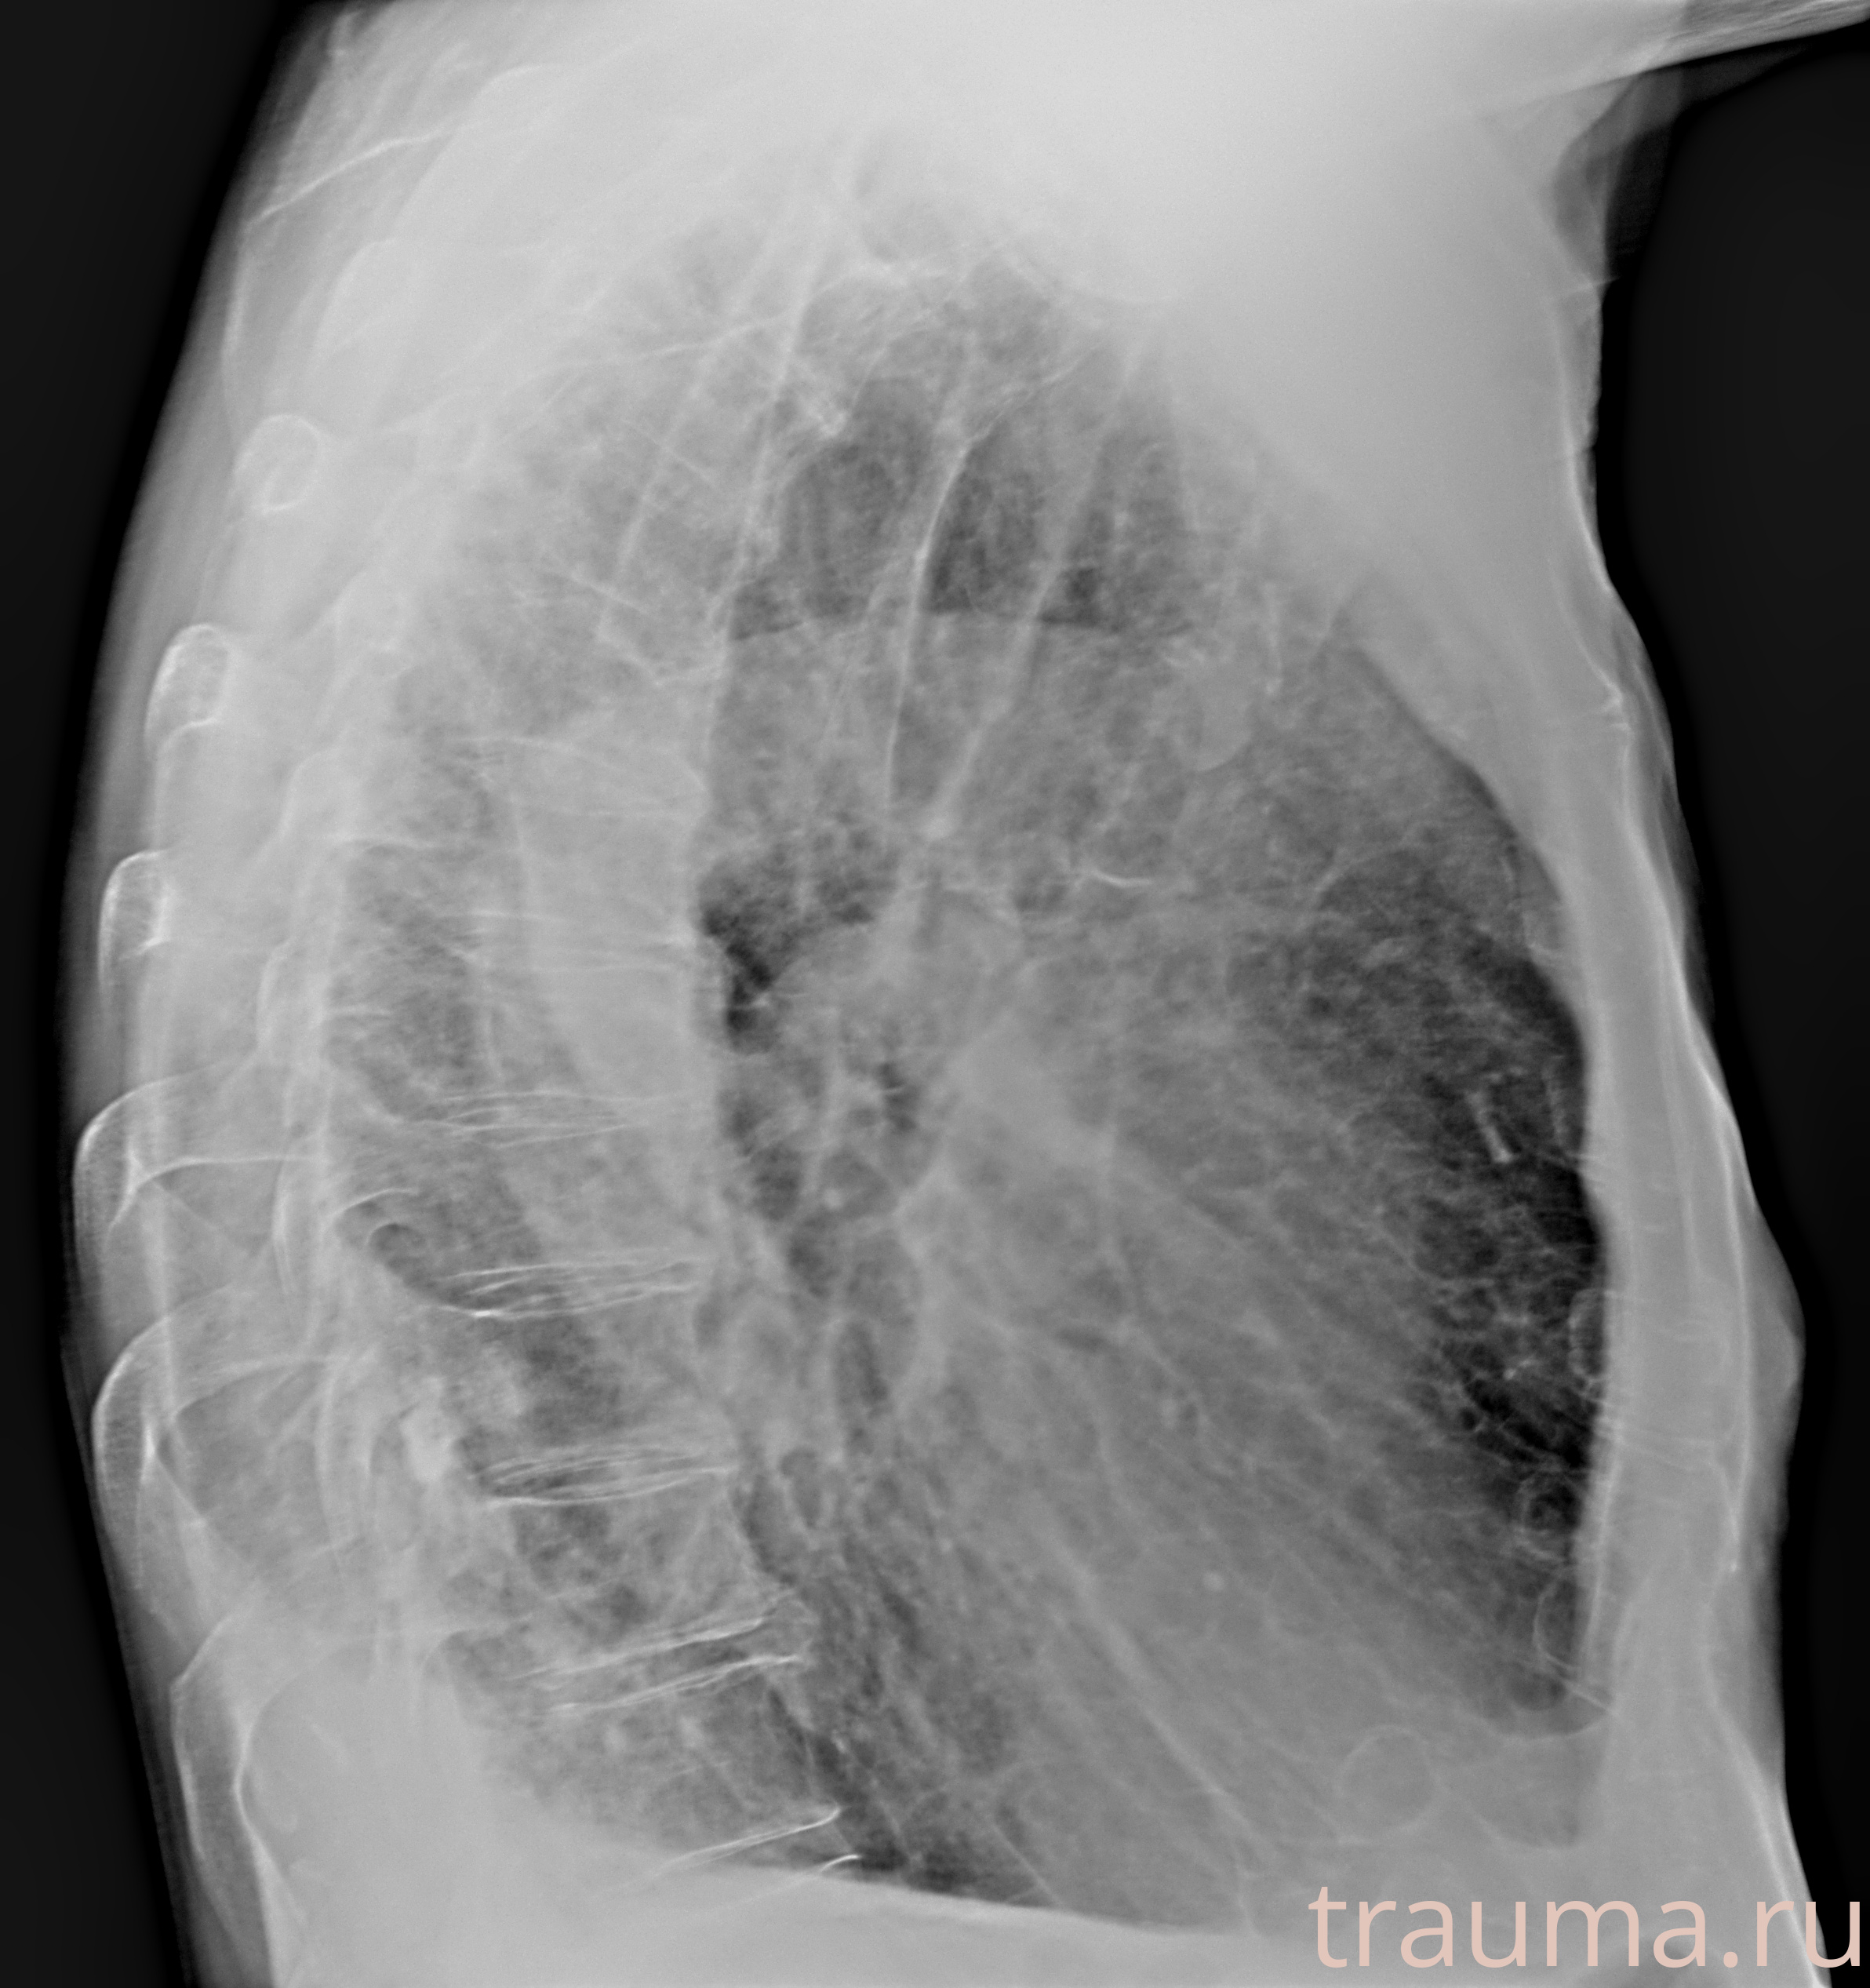

Рентгенограммы

Рентген на дому: по вашему адресу приезжает врач-рентгенолог, травматолог-ортопед с мобильным рентгеновским аппаратом, проводит диагностику травмы или заболевания, делает необходимые рентгенограммы, дает рекомендации по дальнейшему лечению. Получить качественные снимки в домашних условиях возможно благодаря уникальной методике, разработанной МосРентген Центром для института  Склифосовского